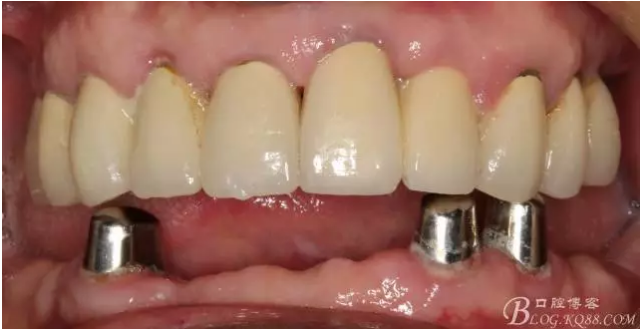

還要有足夠的牙本質(zhì)肩領(lǐng),大家現(xiàn)在可以看到患者的下頜套筒冠還是非常好的

修復(fù)后照片,

患者的口腔衛(wèi)生保持的不好,有大量的軟垢附著,

最近復(fù)查的照片,牙周維護(hù)好一些了,畢竟是一個(gè)80歲的老爺爺了,每次來拄著拐,還要跟著很多人攙扶著過來很不容易了。